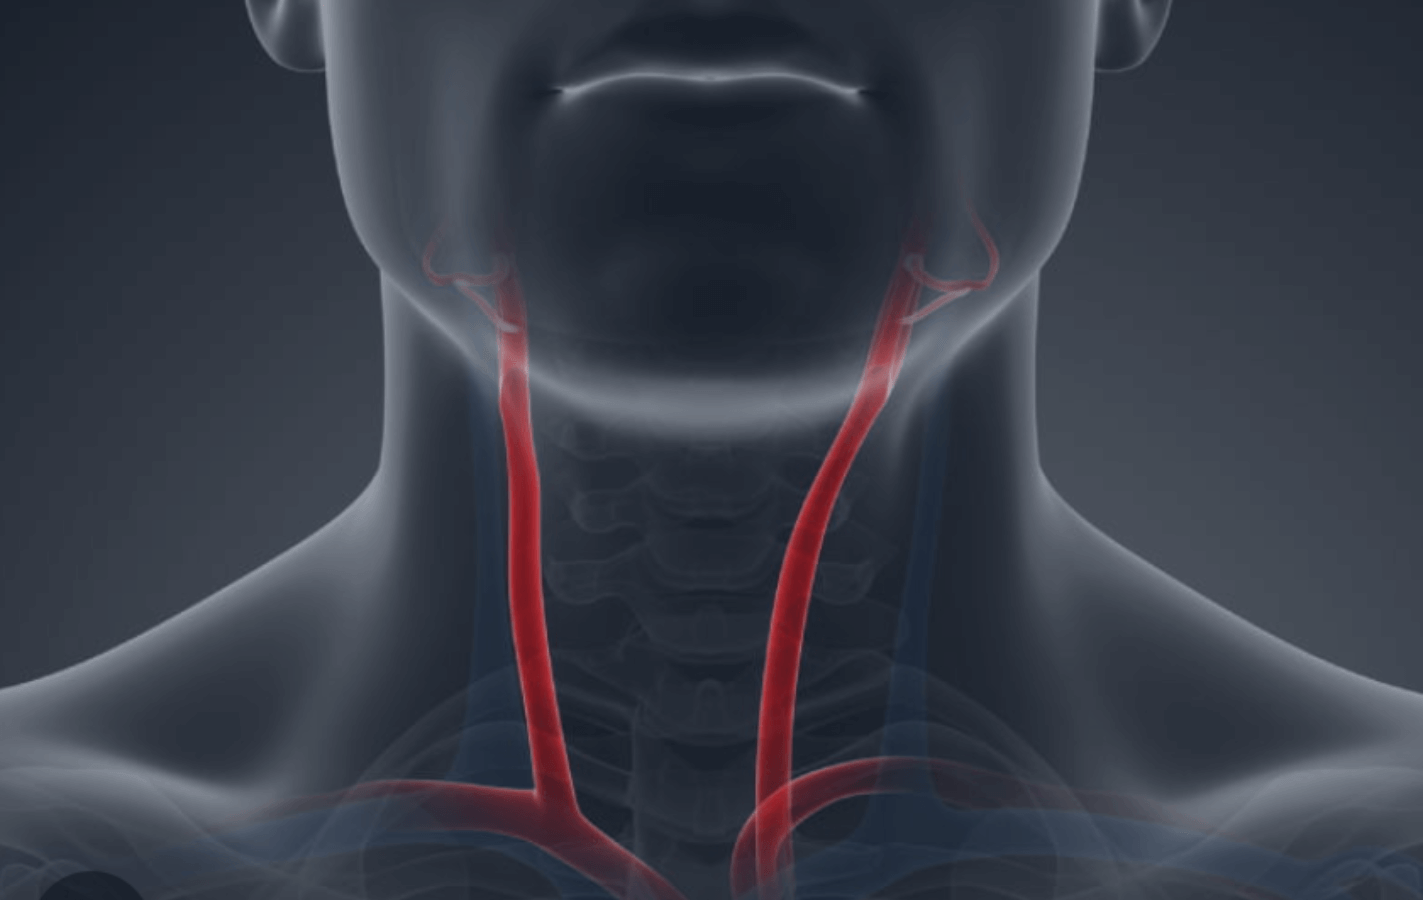

Derrame (AVC)

As artérias carótidas são as responsáveis por transportar o sangue até o cérebro, e se não forem bem cuidadas, podem originar sérias consequências. Um dos casos mais recorrentes é o desenvolvimento da doença carotídea aterosclerótica, que pode resultar em um Acidente Vascular Cerebral Isquêmico (AVCI), popularmente conhecido como derrame, responsável por altos números de mortes no Brasil.